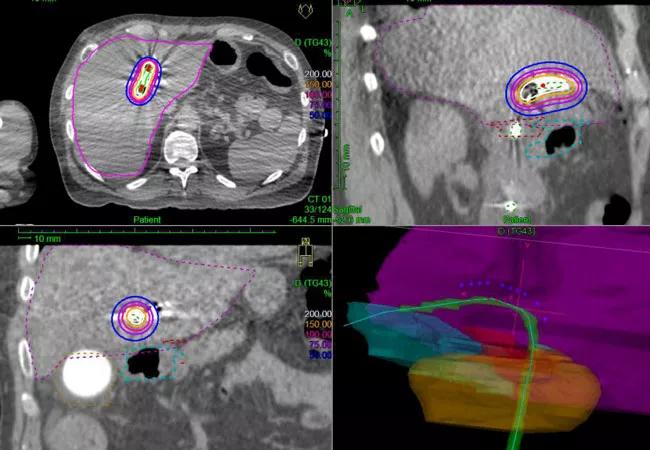

How is hyperfractionated radiotherapy delivered?

Dr. Stephans: We typically use intensity-modulated radiation therapy (IMRT) as the delivery method because it allows us to focus the radiation beam on the tumor and reduce the intensity of radiation to the surrounding healthy tissues. IMRT also delivers radiation at the most geometrically and anatomically favorable angles. The use of multiple beams creates a stronger focal point of radiation, sparing the surrounding normal tissues.

Dr. Stephans: Perihilar cholangiocarcinoma treatment is a three-step process. External hyperfractionated radiotherapy is delivered twice per day, Monday through Friday, for three weeks. Approximately one week after completing external radiation, the patients are admitted for three days and given high-dose brachytherapy, which is delivered internally from within the bile ducts.

In this step, one access catheter is placed in the right bile duct and another in the left bile duct, and a source of radiation is placed inside both catheters. The source delivers radiation at 10 to 15 different positions inside the tumor, and the tumor ultimately receives a very large cumulative dose of radiation.

With the initial 30 external treatments, we are treating the edges of the tumor and the surrounding lymph nodes, while the final three high-precision, high-dose treatments are delivered to the tumor internally.